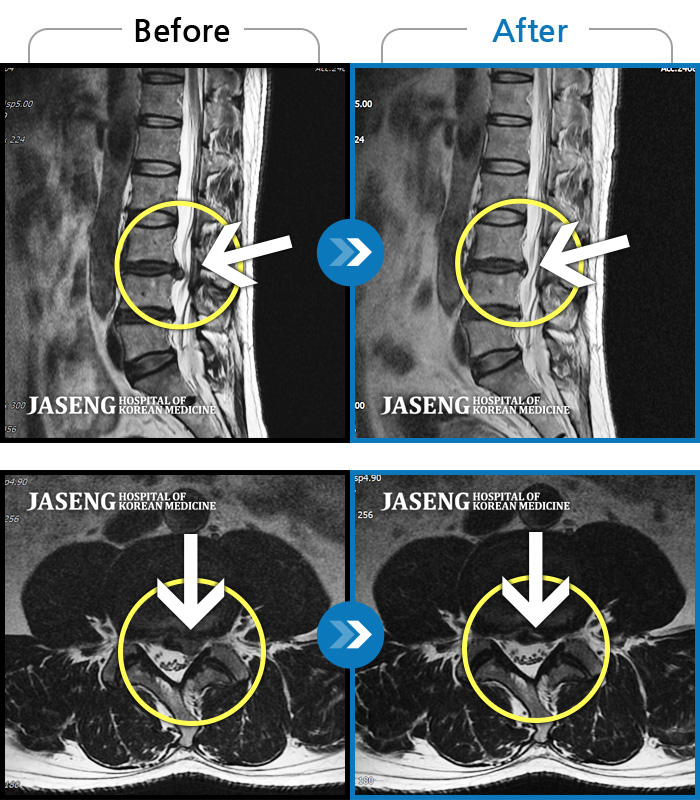

MRI 치료사례

좌측요통 좌측하지방사통으로 타병원에서 8회 주사치료 후 호전 없어서 내원